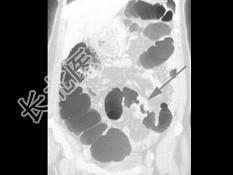

- 单项选择题男,55岁, 左下腹胀痛、并可触及包块,结合图像, 最可能的诊断为 ( )

A、结肠Crohn病

B、结肠癌

C、结肠腺瘤

D、肠结核

E、慢性溃疡性结肠炎